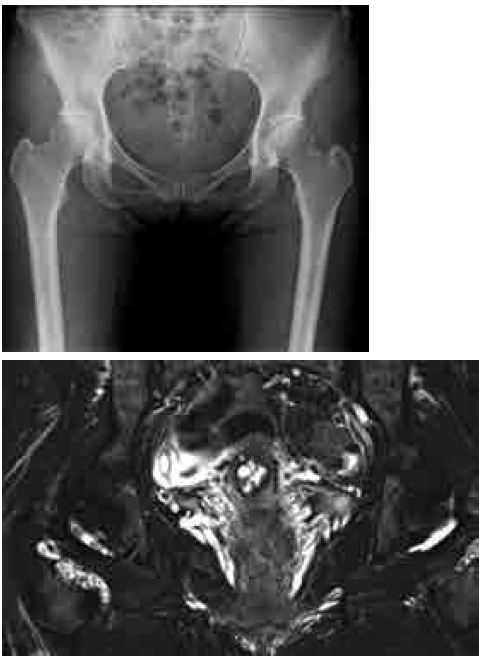

52歳女性。右股関節痛、RA因子・CRP陰性。最も考えられる疾患はどれか。

正解:a

解説:

- 多発性骨様陰影・関節内遊離体が特徴的=滑膜骨軟骨腫症の典型像。

- ちなみに病理分類で Milgram分類というのがある。第1期は関節内に遊離体のみられない滑膜内病変期。第2期は滑膜内病変と関節内遊離体の両者が存在する移行期。第3期は滑膜病変は消退し関節内に多数の遊離体がみられる時期。